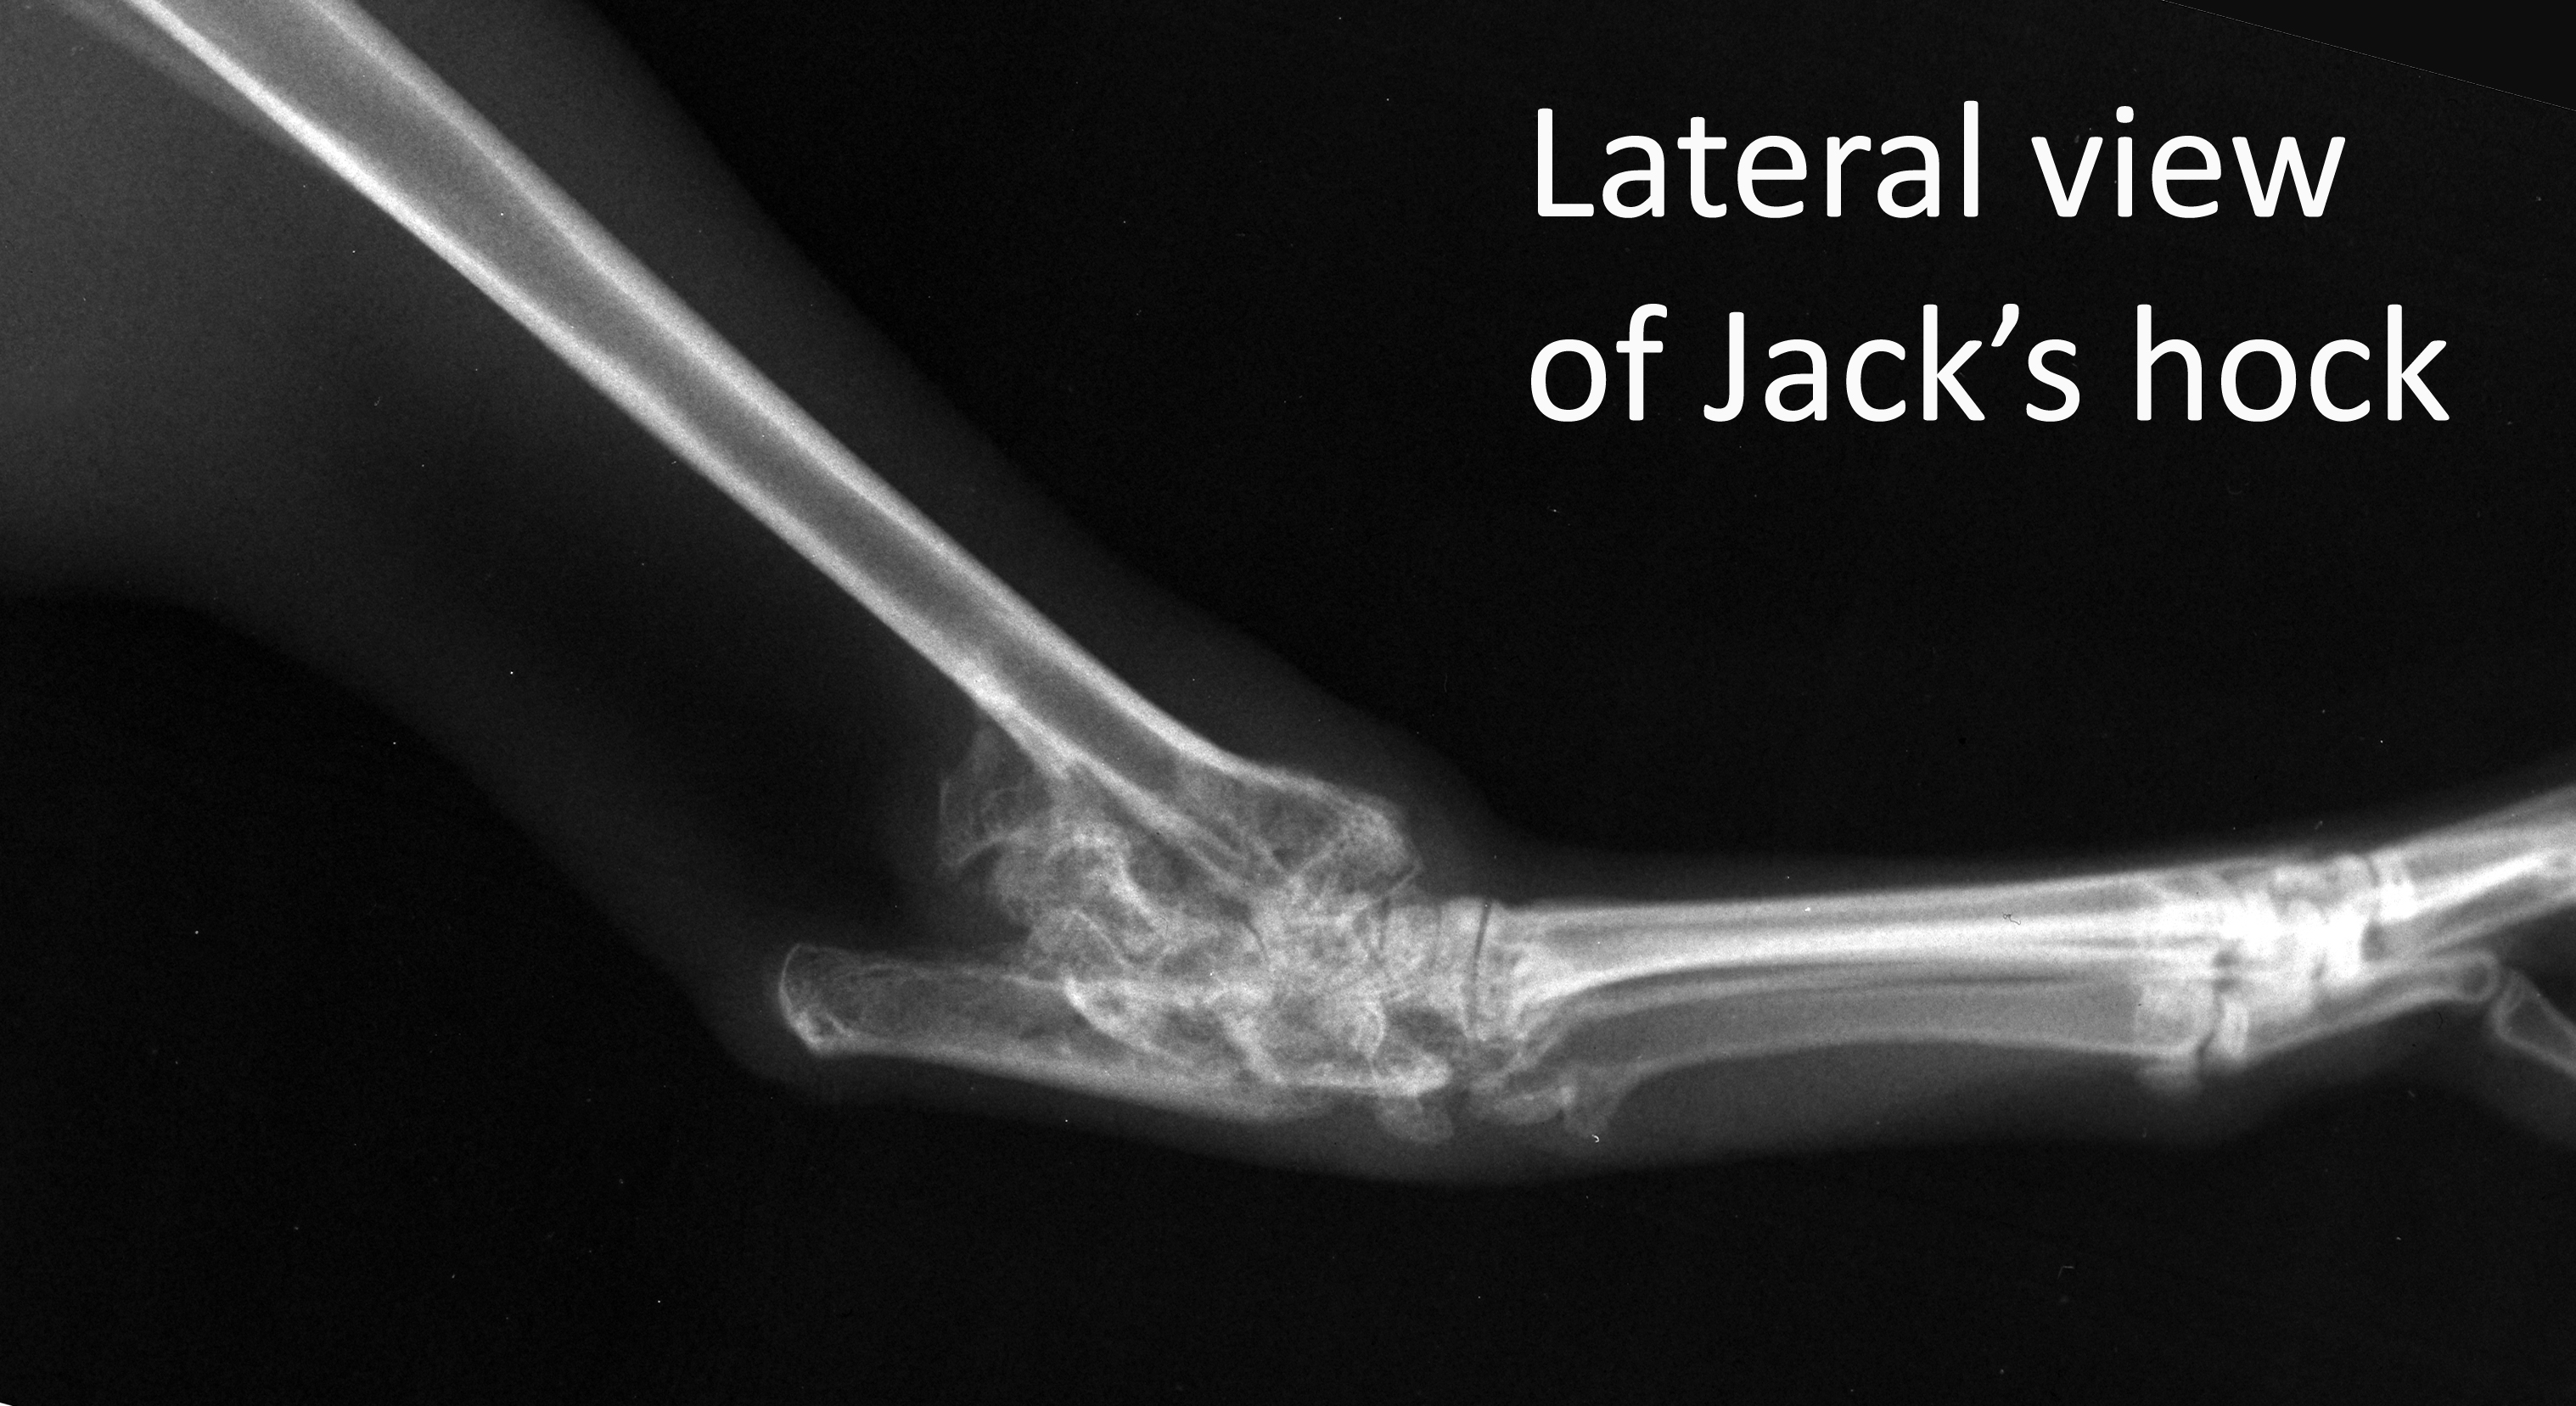

Labelled image of Jack's hock lateral

Radiograph

Orthopaedics

Jack